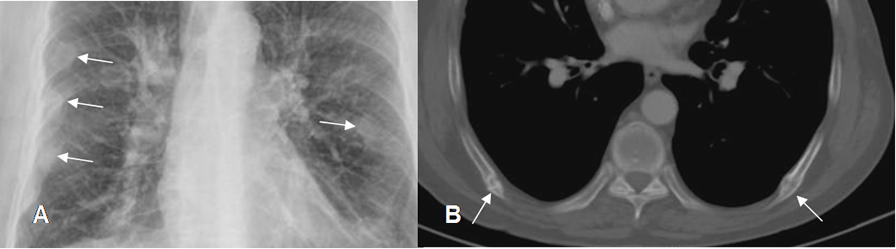

Fig 25. Fractura costal.

A: Rx PA y B: TAC axial. Formación de callos óseos bilaterales, por fracturas costales de evolución crónica.